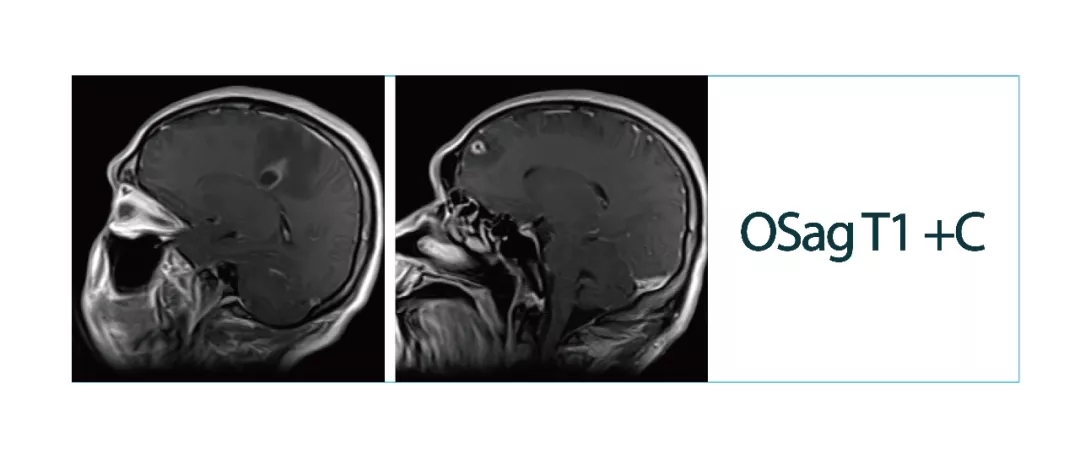

【朗润影像档案】20180413磁共振影像病例分享